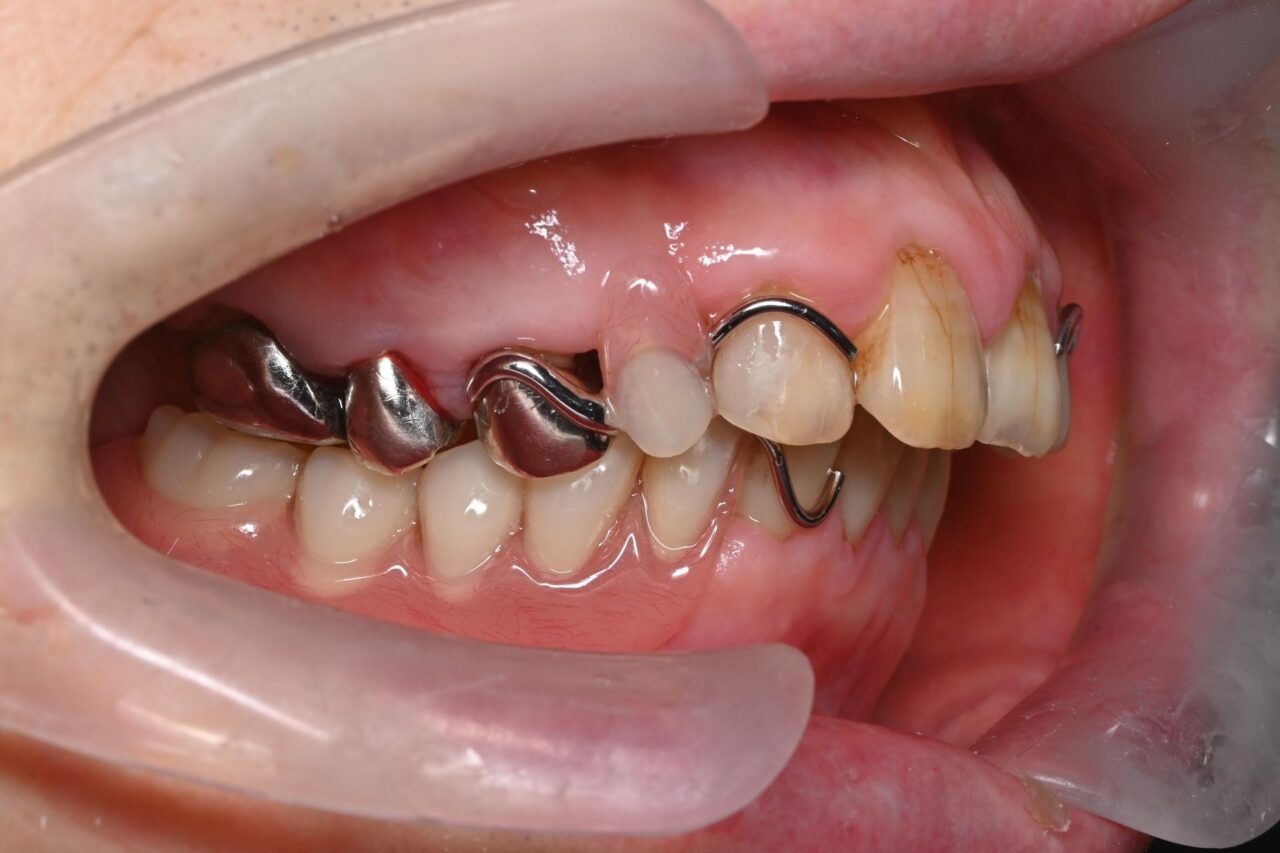

右側

右下には全く歯がありません。

これでは奥歯でお肉が噛めません( ;∀;)